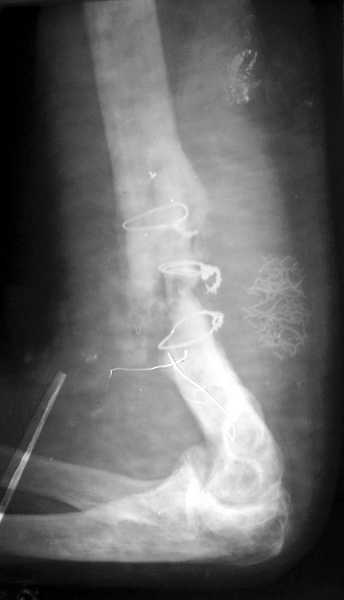

На примере два случая, извиняюсь за качество снимков, снимки и случаи из бывшего союза.

Первая больная с "успехом" была прооперирована 6 раз различными методами открытого и закрытого

остеосинтеза, включая то, что в Кисловодске заезжим австралийским "кудесником" на ложный сустав уложена скорлупа от страусиновых яиц. Последняя операция одиноким локинг плейт в одной из клиник.

Через год по поводу тех же проблем сделали ревизию, оригинальную пластину оставили как есть, только укрепили добавлением еще одной пластины и сделали костную пластику.

Через два месяца увидели признаки консолидации.

Второй случай, также после множественных операций:

пластина, аппарат, серкляж и парез нерва.

Также ревизия, из-за низкого состояния доступ был

сделан через остеотомию локтевого отростка.

Ложный сустав фиксирован двумя локинг плейт с

аутокостной пластикой, также через два месяца увидели признаки консолидации.

Движение в суставе разрешили в две недели.